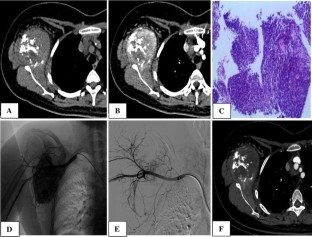

Fig. 1

Fig. 2

Fig. 3